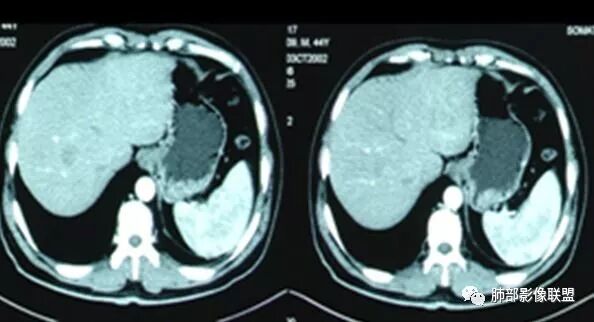

腹部B超及心脏彩超

腹增强CT

脾大,肝内结节中央似有点状血管通过,炎性可能

4.本例肝脏的病灶并未出现典型肝脓肿图像特征,病灶密度及中央血管样结构显然不符合一般的囊肿。应当说,它是感染灶,但并未液化形成脓腔。